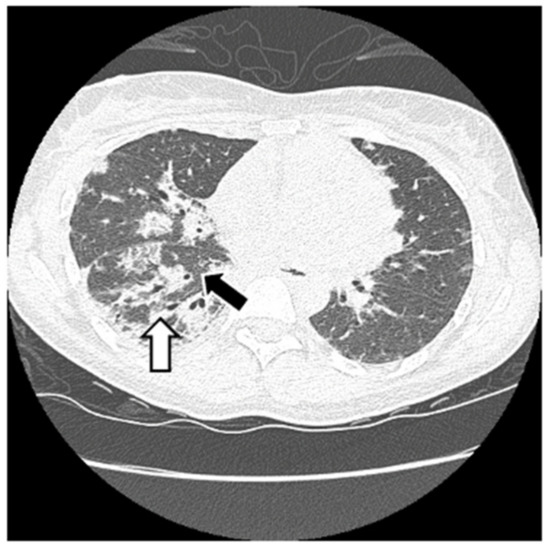

6.2. Histopathologic and Radiographic Findings in Myositis-Associated ILD